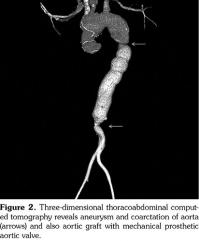

A 26-year-old female patient with eight-year history of TA had undergone Bentall procedure involving composite replacements of aortic root with 30 mm Dacron tube graft and St. Jude, No. 23 mechanical aortic valve (St. Jude Medical Drive. St. Paul, Minnesota, USA) due to severe aortic aneurysm and valve regurgitation seven years ago and presented with chest pain and labile hypertension. She was treated with combined immunosuppressive therapy of prednisolone and azathioprine for five years. Additionally, the patient was on warfarin treatment with a target international normalized ratio between 2-4 for prosthetic aortic valve replacement. On physical examination, she had rhythmic heart beats, 3/6 systolic murmur on the fifth left intercostal space. Her blood pressure on the right arm was 150/96 mmHg and there was no pressure difference between her right arm and legs. Routine blood tests showed that inflammatory markers and white blood cell counts were within normal limits and two blood culture sets taken on admission were negative. Electrocardiography revealed a normal sinus rhythm with a ventricular rate of 75 beats/minute. Comprehensive transthoracic and real-time two- and three-dimensional transesophageal echocardiography showed 2 mm-anterior leaflet perforation with moderate regurgitation on medial side of native mitral valve as well as normal left ventricular function and wall motion, and functionally normal aortic root replacement with mechanical composite aortic valve (Figure 1). There was no annular calcification, and no valvular vegetations were seen. Three-dimensional thoracoabdominal computed tomography revealed aneurysm and coarctation of aorta with diffuse calcifications on the descending aorta (Figure 2). Conventional aortography was performed using a pigtail catheter which revealed an aortic gradient of 15-20 mmHg. Since there was no significant hemodynamic gradient and moderately mitral valve regurgitation, medical treatment was advised. Written informed consent was obtained from the patient.